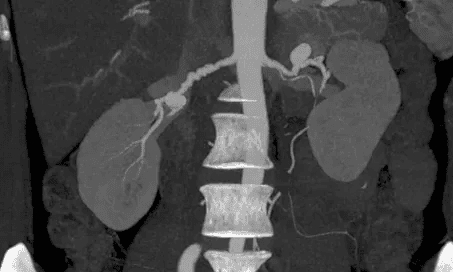

A Angiotomografia vascular permite o estudo dos diversos sistemas arteriais e venosos do corpo humano. Especialmente indicada para avaliação dos grandes artéria como a Aorta, Carótidas e Vasos intracranianos. É fundamental para o diagnóstico e acompanhamento de diversas doenças como aterosclerose, aneurismas e dissecções. Também muito utilizada para programação de correção cirúrgica e percutânea permitindo realizar medidas de precisão para escolha de próteses e fornecendo ao cirurgião informações anatômicas de relevância para a adequada realização dos procedimentos, minimizando intercorrências.